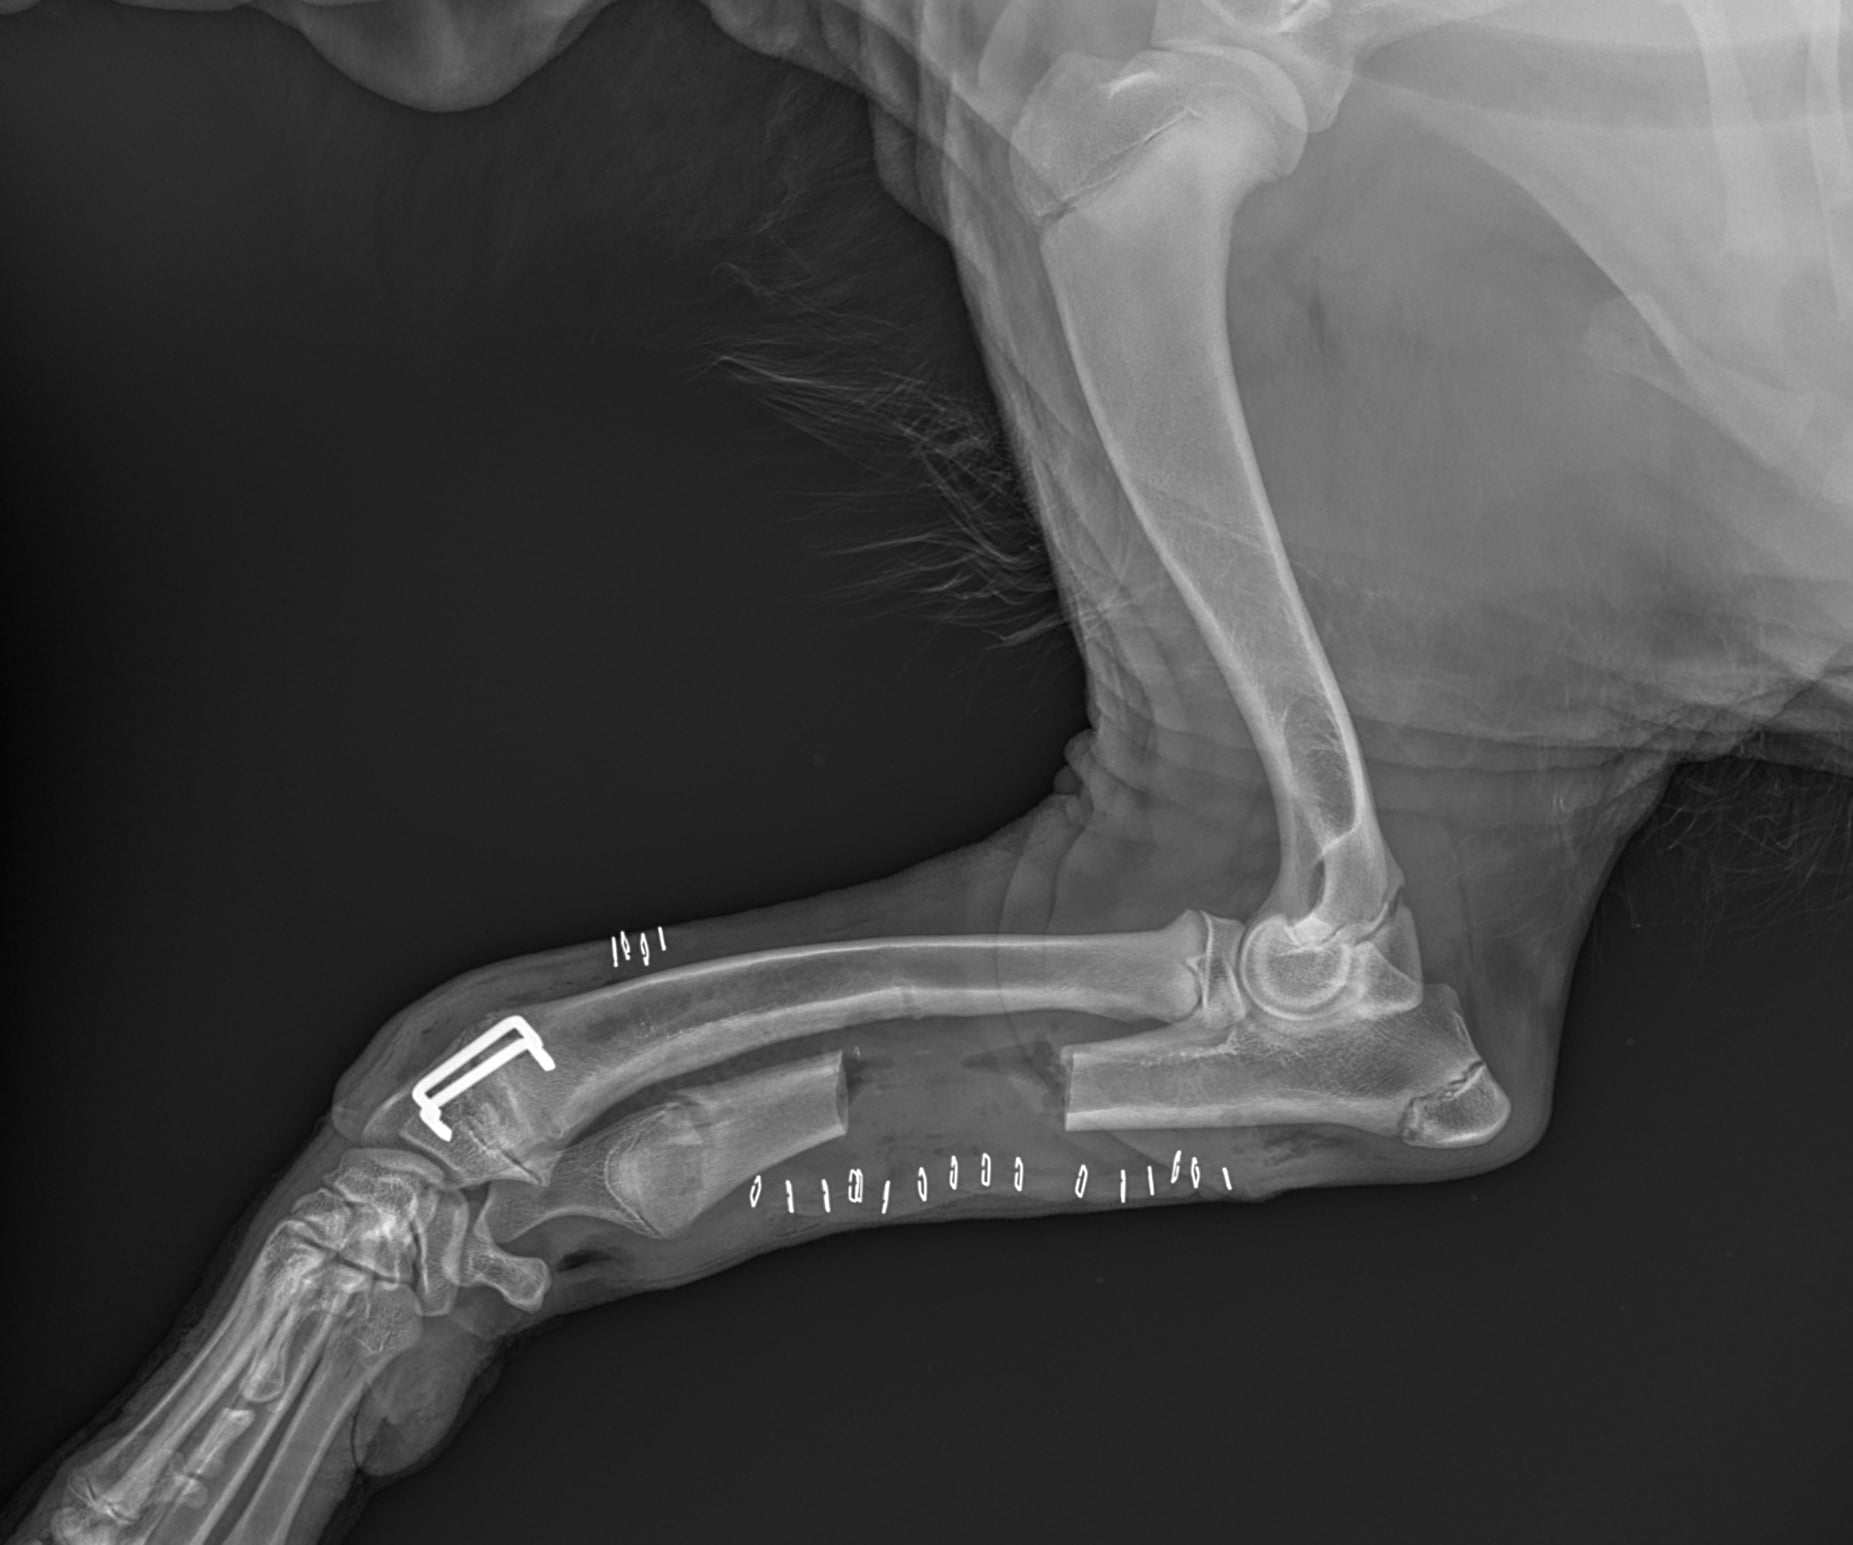

Poniżej prezentujemy zastosowanie klamer kostnych w leczeniu zespołu krzywej kości promieniowej u psa.

Zdjęcia przedstawiają osteotomię kości łokciowej i częściową epifizjodezę kości promieniowej.